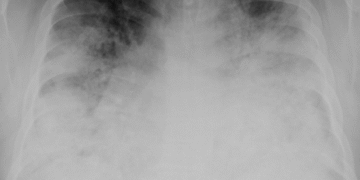

Boala legionară este o infecție pulmonară gravă cauzată de bacteria Legionella pneumophila. Aceasta se transmite prin inhalarea de vapori sau aerosoli de apă contaminată, provenind de obicei din sisteme de climatizare, turnuri de răcire sau fântâni decorative. Simptomele includ febră, frisoane, tuse, dificultăți de respirație și, în cazuri severe, pneumonie.